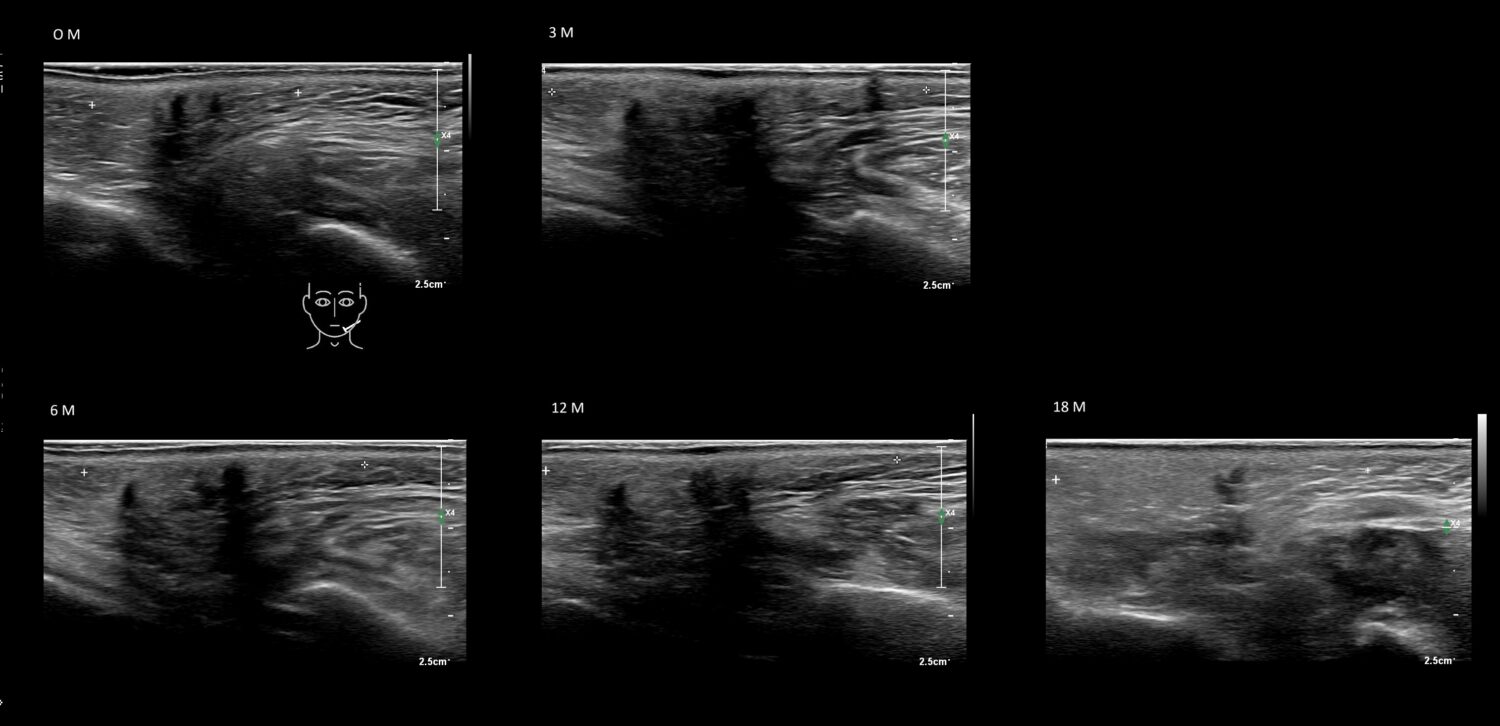

Draw in the image on the right where the fillers are located. To check if your answer is correct, please click on the secondary image.